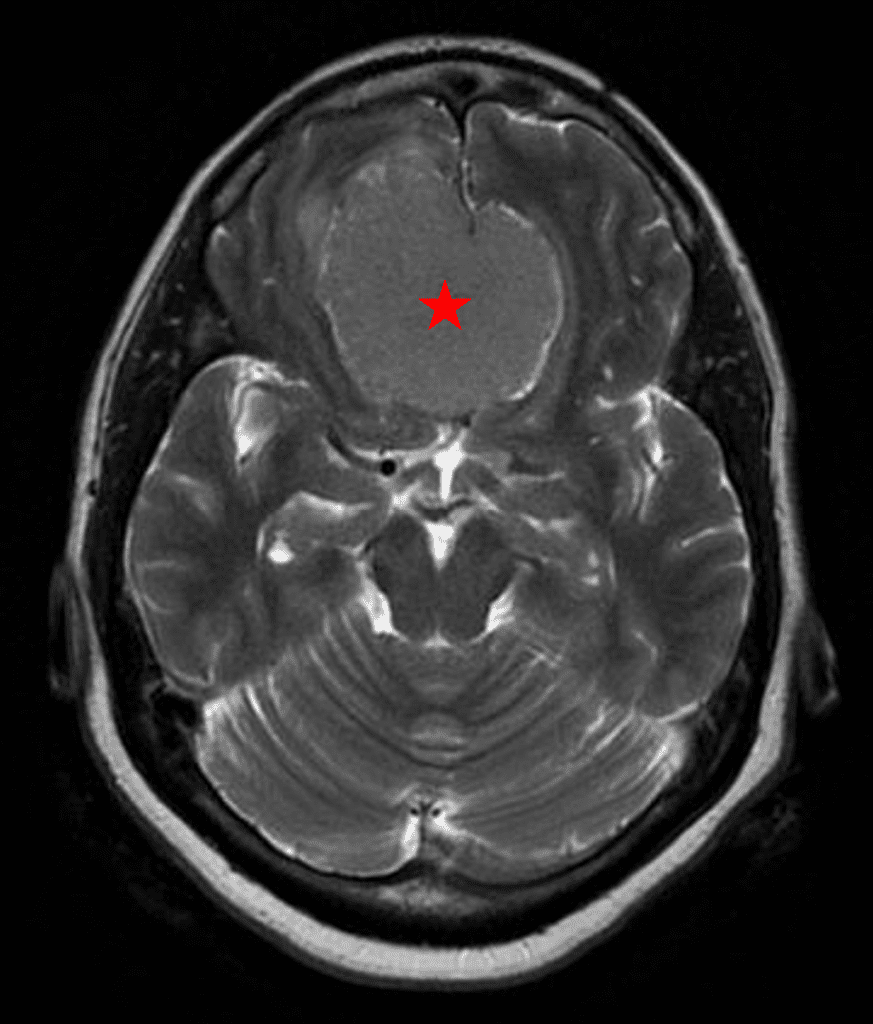

This is a 49-year-old otherwise healthy female who presented with bifrontal and retro-orbital headaches, behavioral changes, and forgetfulness. Symptoms have been progressively worsening over the past month. Her neurologic exam revealed a pronator drift, otherwise was unremarkable. MRI brain demonstrated a large extra-axial homogeneously enhancing mass of the anterior cranial fossa, resulting in significant mass effect and vasogenic edema (Figure 1a and 2a). Imaging was most consistent with a planum sphenoidale meningioma. She was referred to Dr. Xavier Gaudin for neurosurgical evaluation.

Figure 2a – Preoperative MRI demonstrating an extra-axial lesion with surrounding vasogenic edema and mass effect on the frontal lobes.